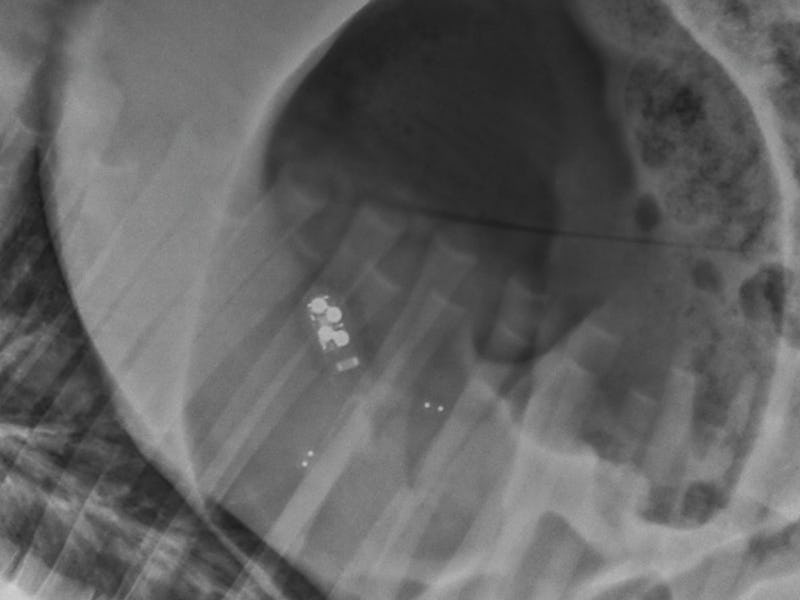

The sensor itself is housed in a swallowable capsule, around the size of fish oil supplement, says Traverso, a gastroenterologist at Brigham & Young Women’s Hospital and medical engineer MIT. The capsule is ingested and settles into the patient’s stomach; the outside coating wears away, leaving the 3-D printed sensor to monitor the body from its core.

The sensor is Bluetooth-enabled for wireless communication with an outside device.

The sensor is currently powered by several minuscule batteries, though the scientists have been considering a model that harvests energy from the G.I. tract.